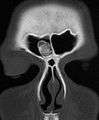

Osteoma of the frontal sinus seen on x-ray

Osteoma of the frontal sinus on CT

Osteoma represents the most common benign neoplasm of the nose and paranasal sinuses. The cause of osteomata is uncertain, but commonly accepted theories propose embryologic, traumatic, or infectious causes. Osteomata are also found in Gardner's syndrome. Larger craniofacial osteomata may cause facial pain, headache, and infection due to obstructed nasofrontal ducts. Often, craniofacial osteoma presents itself through ocular signs and symptoms (such as proptosis).[1]